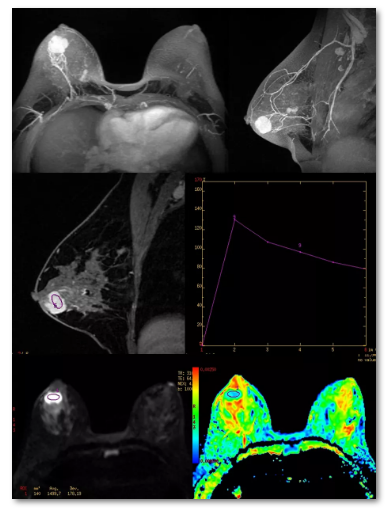

具有良好的软组织分辨率和无射线辐射特点,对乳腺检查具有独到的优势。

■乳腺MRI检查具有以下优势:

·软组织分辨率高,对发现乳腺病变具有较高的敏感性,特别适于观察致密型乳腺内的肿瘤;

·MRI三维成像使病灶定位更准确、显示更直观;

·多参数成像,不仅可以显示病变的形态学信息,还可以提供病灶血流动力学、水分子扩散及肿瘤代谢等功能学信息,有助于良、恶性病变的鉴别及疗效评估;

·对多中心、多灶性病变的检出较为敏感,对胸壁侵犯的观察以及对腋窝、内乳区的显示较为敏感,可为乳腺癌的准确分期和临床制订治疗方案提供可靠的依据;

·对以腋窝淋巴结转移为首诊的隐匿性乳腺癌患者,有助于发现乳腺内原发灶;

·可准确观察乳房假体位置,确认有无破裂等并发症;

·无射线辐射性。